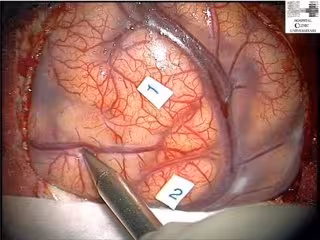

Imagen del curso de Neurocirugía.

El núcleo más importante de actividad es el estudio anatómico cerebral con demostraciones de los profesores y prácticas de los participantes.